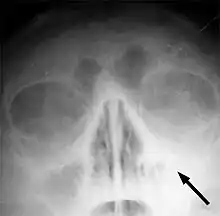

Imaging by either X-ray, CT or MRI is generally not recommended unless complications develop.[47] Pain caused by sinusitis is sometimes confused for pain caused by pulpitis (toothache) of the maxillary teeth, and vice versa. Classically, the increased pain when tilting the head forwards separates sinusitis from pulpitis.